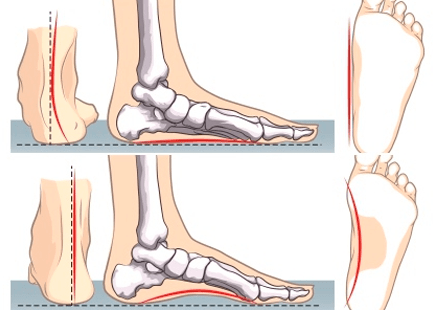

• Defectos de apoyo

- Pie plano

- Pie cavo

- Pie aducto